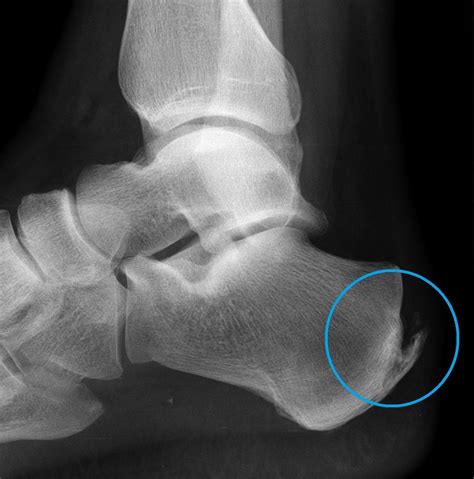

Diagnosing heel spurs typically involves a combination of physical examination and imaging tests. A healthcare provider will assess the foot for tenderness, swelling, and range of motion. Imaging tests such as X-rays, ultrasound, or magnetic resonance imaging (MRI) may be used to confirm the presence of a heel spur and rule out other potential causes of heel pain.